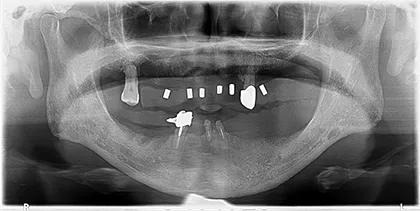

- BEFORE

| 年代・性別 | 70代・男性 |

|---|---|

| 主訴 | 今使っている入れ歯が合わず、嚙むと痛い |

| 治療部位 | 15~26、36、45 |

| 治療内容 | 上下顎インプラント埋入術(上顎5本、下顎2本)を、2回に分けて実施。26部はソケットリフトを適用し、2回法で実施。他部位は1回法。 |

| 金額(税込) | 29,000,000円(税込) |

| 治療期間 | 7カ月(インプラント埋入から上部構造装着まで) 12年経過例(2024年3月時点) |

| リスクと副作用 | 手術部位の腫脹、疼痛 マスダ歯科のインプラント詳細はこちら |